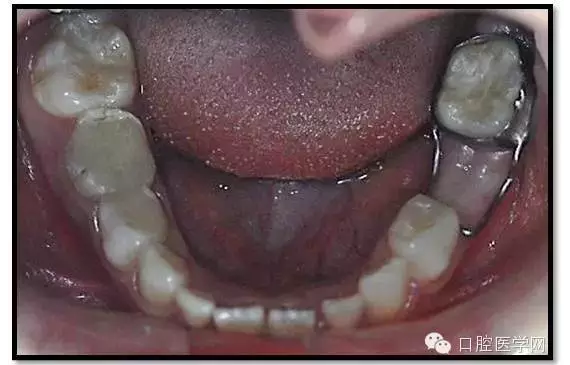

討論:

1、根分歧處病變姑息保留牙的治療及轉(zhuǎn)歸。 75牙體缺損過大,根分岐大面積透射影并累及根尖周。故拔除后間隙保持。84、85初診時已做過根管治療,有繼發(fā)齲,牙根吸收較多,可見大面積的根分歧病變,但根尖無病變,考慮44、45表面骨硬板連續(xù),故只對患牙進行了繼發(fā)齲充填治療,姑息保留。3個月復查時,85O、84DO充填完好,邊緣密合,叩(-),不松,齦無紅腫。7個月復查時85O、84DO充填完好,邊緣密合,叩(-),不松,齦無紅腫。X線:84、85根分歧透射影,44、45骨硬板連續(xù)。 回顧整個治療過程,應定期復查84、85姑息保留牙,且間隔時間不宜過長。觀察根分歧病變的恢復情況,一旦發(fā)現(xiàn)恒牙胚受累及,則需采取積極措施。

2、75OL、85O、84DO發(fā)生根尖及根分歧病變原因 追溯75OL、85O、84DO就診之前病史,84是因慢性根尖周炎1年前行根管治療,治療當時根充滿。75、85因慢性牙髓炎1年前行根管治療,治療當時根充滿。這幾個牙當時牙體缺損均較大,未行預成冠修復,隨后充填體脫落,發(fā)生繼發(fā)齲,患兒1年一直未定期復診,導致口腔內(nèi)感染通過冠方造成根分歧和根尖的炎癥。所以總結(jié)以上,對于大面積齲壞牙根管治療后應定期復查,并行預成冠修復。